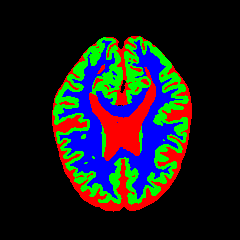

• OASIS-1 [34]: Derived from the Open Access Series of Imaging Studies, this dataset comprises T1-weighted MRI scans from 421 subjects (aged 18–96). The images were acquired with a resolution of 176×208176\times 208 pixels and a slice thickness of 1.25 mm (TR=9.79.7 ms, TE=4.04.0 ms, TI=2020 ms). Following standard protocols, we utilize the provided manual segmentation masks for Cerebrospinal Fluid (CSF), Grey Matter (GM), and White Matter (WM).

7 Qualitative Evaluation

Fig. 8 and Fig. 10 provide qualitative comparisons on the OASIS-1 and MRBrainS13 datasets, respectively. It is visually evident that the baseline predictions (c) and standard augmentations (e.g., (d), (g), (i)) frequently suffer from noisy artifacts, blurred boundaries, and mis-segmentation of intricate anatomical structures. In stark contrast, our ”Ours+” enhanced methods (e.g., (e), (h), (k)) consistently produce segmentation maps that are visibly cleaner, more spatially coherent, and demonstrate significantly sharper adherence to the Ground Truth (b). This superior fidelity is particularly noticeable in the complex sulcal patterns and holds true across all three backbones (rows), confirming that our framework yields more robust and anatomically plausible results.